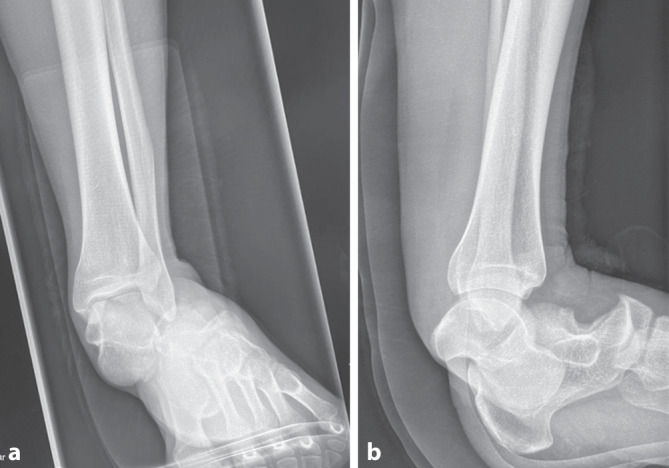

Background: Subtalar dislocations (simultaneous dislocations of the talocalcaneal and talonavicular joints) without concomitant fracture are rare and account for 1-2% of all dislocations. The treatment has been described in several case reports and consists primarily of closed reduction with the patient under anesthesia followed by immobilization.

Case: A 30-year-old male patient sustained a multidimensional nonfractured dislocation of the ankle joint with a predominantly subtalar component (luxatio subtalolateralis) while climbing. As it turned out later, a closed reduction was not possible due to interposition of the tendons of the posterior tibialis muscle and the flexor digitorum pedis longus muscle, so that an open reduction had to be performed. The full extent of the injury could only be assessed during the surgical exploration. The patient was treated in an external fixator for 12 weeks. Subsequently, physiotherapy was initiated. After only 6 months postoperatively the patient showed good mobility, functionality and resilience in the affected ankle joint. After 30 months the patient was free of symptoms. The prolonged immobilization after subtalar dislocation using an external fixator over a total period of 12 weeks, as performed in this case report, demonstrated good long-term functional outcomes.